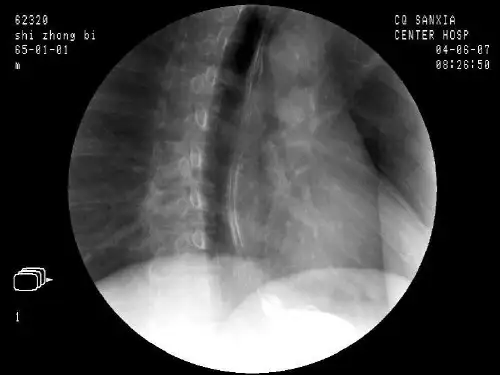

胃镜图谱(正常和常见胃病图谱)-36张课件正常胃镜下所见正常胃镜下所见胃体粘膜皱襞胃体粘膜皱襞胃底贲门胃底贲门胃角胃角幽门前区幽门前区幽门幽门十二指肠球部十二指肠球部十二指肠降部十二指肠降部十二指肠乳头十二指肠乳头十二指肠乳头2十二指肠乳头2消化性溃疡内镜图谱消化性溃疡内镜图谱胃溃疡胃溃疡十二指肠溃疡十二指肠溃疡胃角溃疡胃角溃疡十二指肠溃疡十二指肠溃疡胃溃疡 H 期胃溃疡 H 期 8 82 2 岁男性间歇性的岁男性间歇性的消化不良胃镜下见消化不良胃镜下见胃体近端大溃疡倒胃体近端大溃疡倒镜时明显病理活检镜时明显病理活检为良性虽然后者无为良性虽然后者无消化道出血史在溃消化道出血史在溃疡面上可见一血管斑疡面上可见一血管斑点提示至少有出血点提示至少有出血倾向倾向45 岁男性在服用糖皮质45 岁男性在服用糖皮质激素治疗类风湿性关节激素治疗类风湿性关节炎未用NSAIDs 症炎未用NSAIDs 症状主要为消化不良胃状主要为消化不良胃镜下见胃窦1cm 溃疡溃镜下见胃窦1cm 溃疡溃疡表浅边缘光滑良疡表浅边缘光滑良性性62 岁男性服用布洛芬62 岁男性服用布洛芬后出现腹痛呕吐后出现腹痛呕吐贫血和体重下降胃贫血和体重下降胃镜下见胃窦15-2cm 溃镜下见胃窦15-2cm 溃疡贯通胃壁全层疡贯通胃壁全层病理良性Hp 阳性病理良性Hp 阳性Dieulafoys 病Dieulafoys 病 74 岁女74 岁女性以呕性以呕血入院血入院胃镜下见胃镜下见食管胃交食管胃交界下方脉界下方脉冲样出血冲样出血倒镜时倒镜时明显明显血柱由粘血柱由粘膜破损处膜破损处喷出未喷出未见溃疡见溃疡以热探头以热探头灼烧后止灼烧后止血未再复发复发上 7 70 0 岁女岁女上性以呕血性以呕血入院倒镜入院倒镜时见胃体近时见胃体近端病灶有持端病灶有持续性血流续性血流非脉冲样非脉冲样下病灶处下病灶处以冰水反复以冰水反复冲洗出血冲洗出血暂时止住发现下面有发现下面有一突出的血一突出的血管未见溃管未见溃疡疡门脉高压性胃病门脉高压性胃病门静脉高压患门静脉高压患者胃底体粘者胃底体粘膜典型的斑点膜典型的斑点状鳄鱼皮样状鳄鱼皮样改变肉眼下改变肉眼下与胃炎相似与胃炎相似病理呈典型的病理呈典型的伴炎性活动的伴炎性活动的淤血改变为淤血改变为消化道出血的消化道出血的常见原因之一常见原因之一胃癌胃癌胃溃疡恶变胃溃疡恶变溃疡型胃癌溃疡型胃癌其他胃的疾病其他胃的疾病贲门粘膜撕裂伤贲门粘膜撕裂伤 76 岁男76 岁男性表性表现为贫现为贫血和大血和大便隐血便隐血试验阳试验阳性胃性胃镜下胃镜下胃窦胃窦胃底胃底胃体均可体均可见明显见明显的毛细的毛细血管扩血管扩张张 70 岁男 70 岁男性因性因上腹痛上腹痛行胃镜行胃镜检查检查胃窦部胃窦部见血管见血管扩张扩张内镜下蛔虫的图片内镜下蛔虫的图片十二指肠球部粘膜十二指肠球部粘膜十二指肠球部粘膜2 十二指肠球部粘膜2十二指肠上角上曲十二指肠上角上曲。